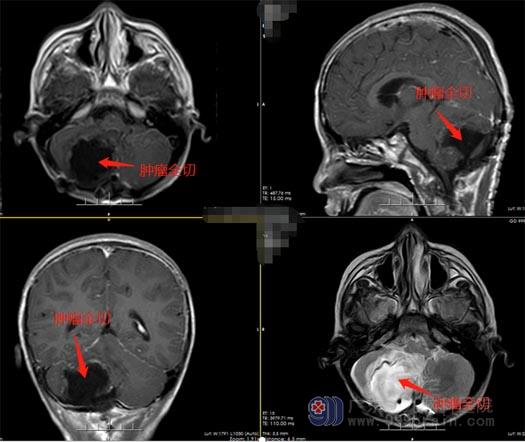

广东三九脑科医院鲁明副院长了解完小文的情况后也意识到事情不简单,立即安排小文进行了详细的检查,王国良主任带领外五科的专家团队进行了讨论,最后一致认为手术是最佳治疗方案,而且达到了刻不容缓的地步。在得到家属同意后,给小文实施了右侧小脑占位切除术,显微镜下全切肿瘤,手术顺利结束。

▲术后

手术很成功,术后小文各项神经功能都正常,肢体活动也没问题,看着逐渐恢复的儿子,父母揪着的心缓缓放下……